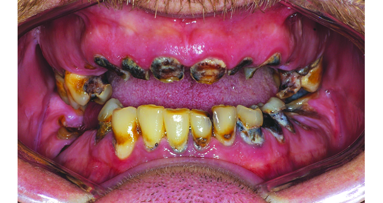

Her chief complaint was to improve her aesthetics and comfort with a desire for a permanent and quick solution to replace her failing dentition. She also desires a reduction of her maxillary anterior gummy smile in the final prosthesis. She arrived at our office for a third surgical consult for an immediate load maxillary and mandibular hybrid restoration using the Straumann Pro Arch treatment concept (tilting of the distal implants to avoid anatomic structures of the maxillary sinus, mandibular mental foramina). This treatment concept reduced the need for additional surgeries and number of implants needed to provide a fixed hybrid restoration with a first molar occlusion. A medium to high lip line was noted upon a wide smile with a bi-level plane of occlusion. Also noted was supraeruption of her maxillary and mandibular anterior teeth (FDI: #12, 11, 21, 22 and #41–43, US: #7–10 and #25–27) creating a deep bite of 6 mm (Fig. 2). A Class I canine relationship was recorded with 6 mm overjet and 6 mm overbite. Due to her medication-related dry mouth issue, generalized recurrent caries were noted. Periodontal probing depths ranged generally from 4–7 mm in the maxillary jaw and from 4 to 6 mm in the mandibular jaw with moderate to severe marginal gingival bleeding upon probing in both jaws. Tooth #6 (FDI: #13) was noted to have a vertical fracture clinically. There was generalised heavy fremitus in her maxillary teeth and mobilities ranging from 2–3 degrees on the following teeth: #3, 7 thru 13, 20–26 and 29 (FDI: #16, 12, 11, 21–25, 31–35, 41–42 and 45). Her compliance profile was good with her previous dentists, however, she states that she has always had “issues with my gums.”

The tentative treatment plan discussed at the initial visit with the patient and her husband included the following diagnosis: generalised moderate to advanced periodontitis; generalised recurrent caries related to medication-related dry mouth; posterior bite collapse with loss of occlusal vertical dimension (“mutilated dentition”). Prognosis: all remaining teeth are hopeless.